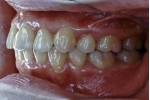

| マルチブラケット終了時